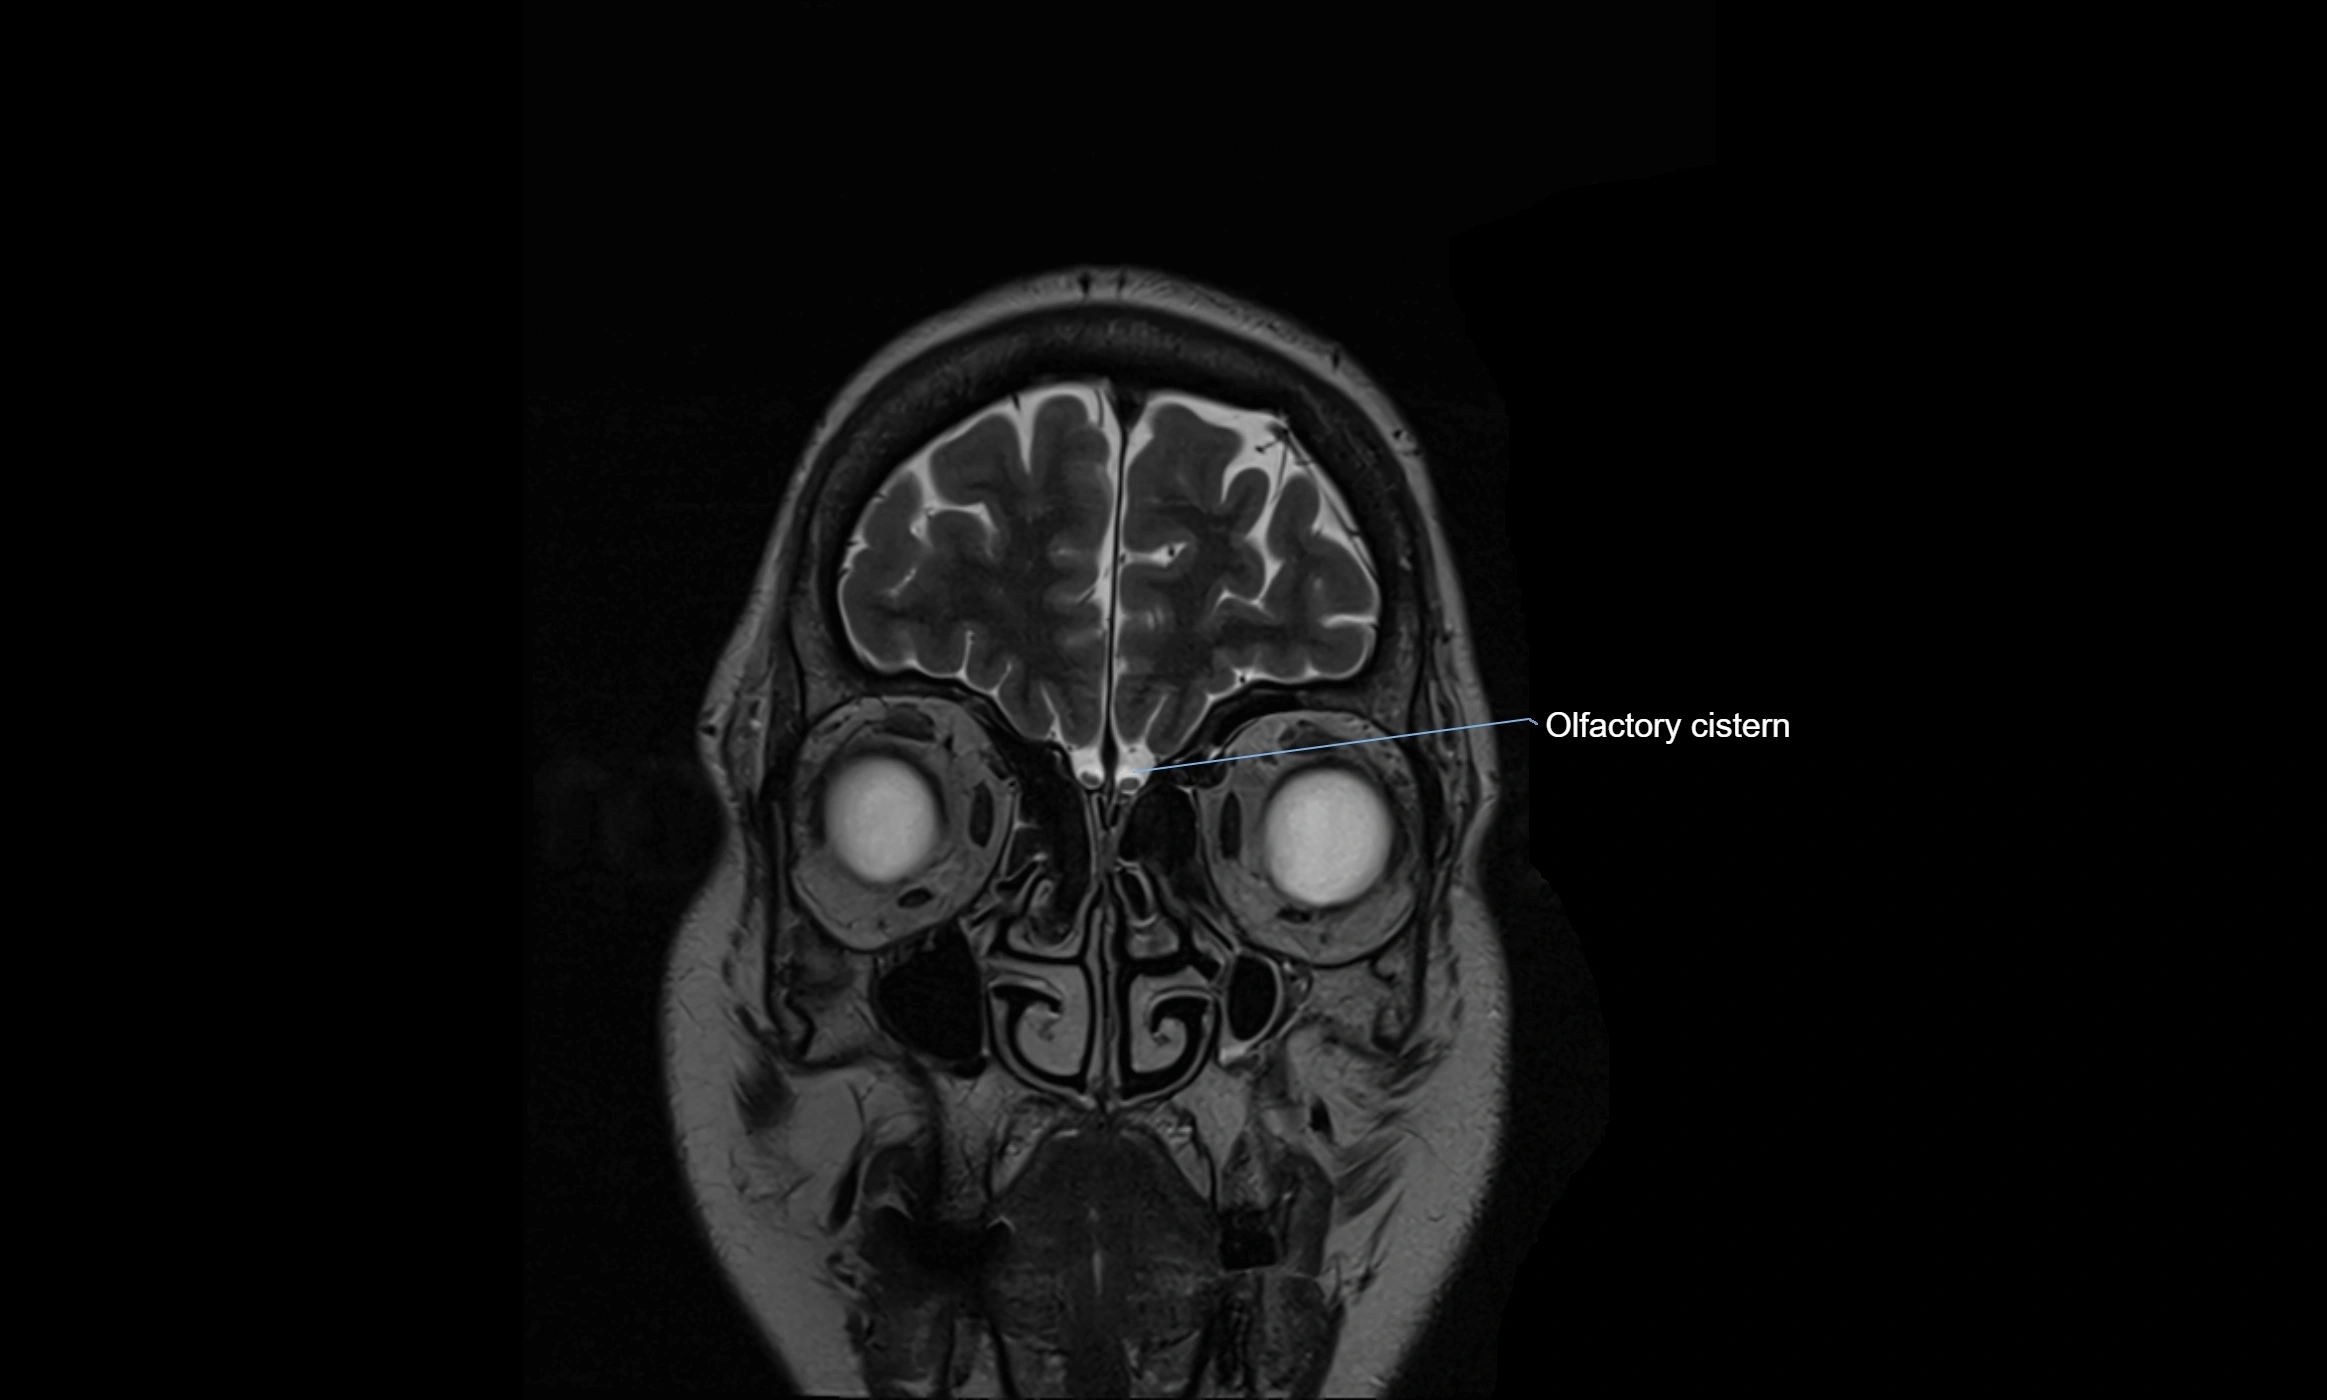

MRI images

image